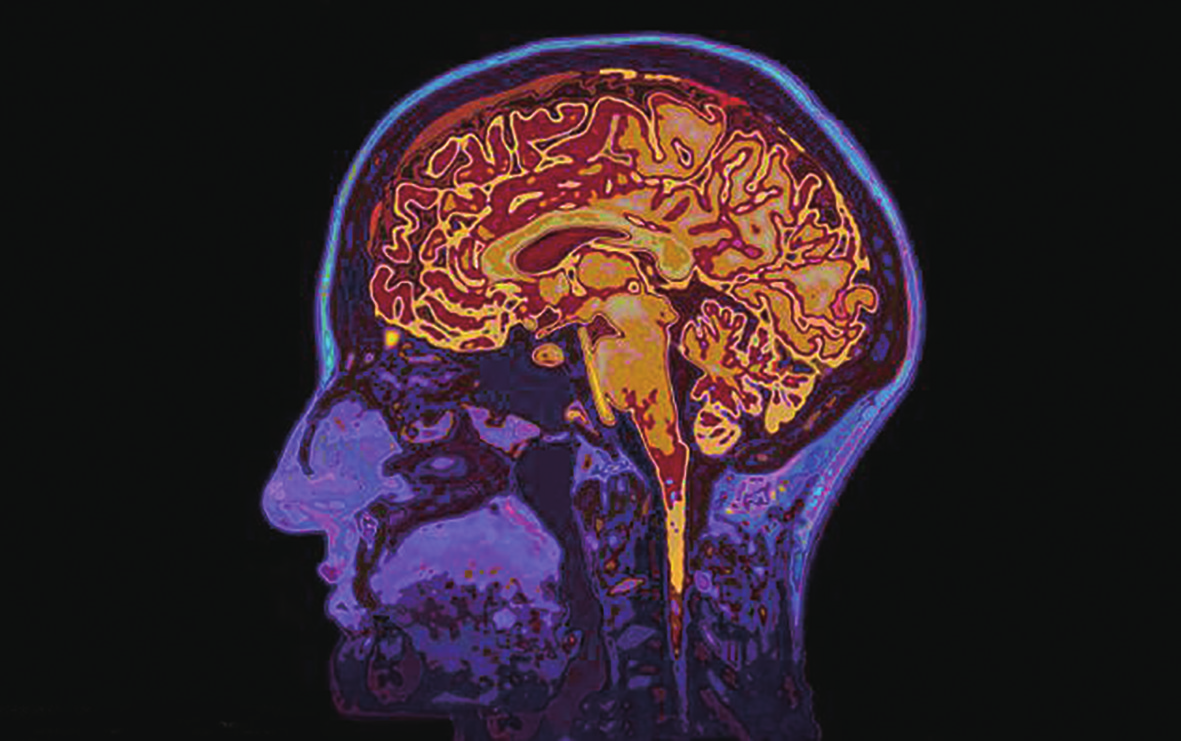

在最近这次实施中,研究人员利用功能性核磁共振成像技术,对1 7名志愿者的大脑进行了扫描,并观察大脑中血液氧饱和水平的变化。当扫描仪探测到受试者处于高度自信状态时,研究人员就会给志愿者小小的奖励,通过这种方式提升志愿者的自信心。当然,类似的技术同样也可以用于降低人的自信心,即当人的大脑处于较低自信状态时给予奖励。